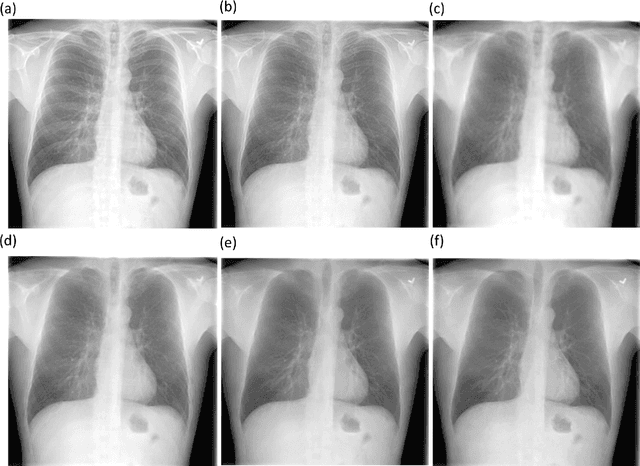

Abstract:Chest X-rays are the most commonly performed diagnostic examination to detect cardiopulmonary abnormalities. However, the presence of bony structures such as ribs and clavicles can obscure subtle abnormalities, resulting in diagnostic errors. This study aims to build a deep learning-based bone suppression model that identifies and removes these occluding bony structures in frontal CXRs to assist in reducing errors in radiological interpretation, including DL workflows, related to detecting manifestations consistent with tuberculosis (TB). Several bone suppression models with various deep architectures are trained and optimized using the proposed combined loss function and their performances are evaluated in a cross-institutional test setting. The best-performing model is used to suppress bones in the publicly available Shenzhen and Montgomery TB CXR collections. A VGG-16 model is pretrained on a large collection of publicly available CXRs. The CXR-pretrained model is then fine-tuned individually on the non-bone-suppressed and bone-suppressed CXRs of Shenzhen and Montgomery TB CXR collections to classify them as showing normal lungs or TB manifestations. The performances of these models are compared using several performance metrics, analyzed for statistical significance, and their predictions are qualitatively interpreted through class-selective relevance maps. It is observed that the models trained on bone-suppressed CXRs significantly outperformed (p<0.05) the models trained on the non-bone-suppressed CXRs. Models trained on bone-suppressed CXRs improved detection of TB-consistent findings and resulted in compact clustering of the data points in the feature space signifying that bone suppression improved the model sensitivity toward TB classification.